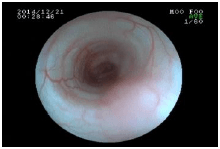

内視鏡を使った呼吸器の検査

内視鏡は胃腸以外にも、喉や気管などの呼吸器の検査・処置にも使われます。

![]() 気管内のできもの(矢印) |